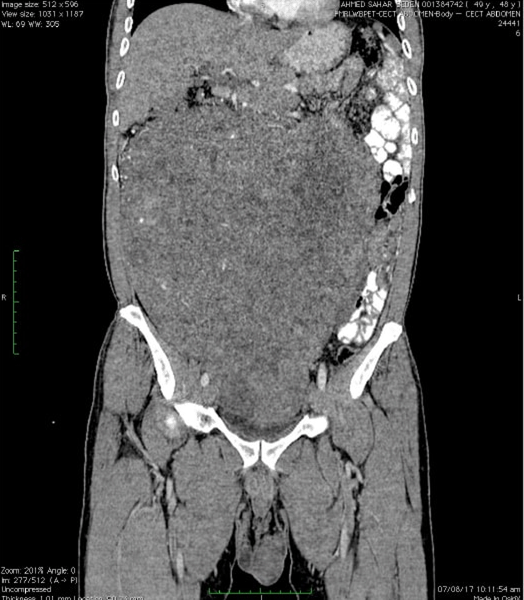

PET-CT scan showed a 26.3x24.3x11.3 cm, abdominopelvic mass extending into abdominopelvic cavity with splaying of large and small bowel and indenting right kidney and IVC, Displacing right lobe of liver (Figure 1) and (Figure 2).

Figure 2: Coronal view of contrast-enhanced computed tomography scan.